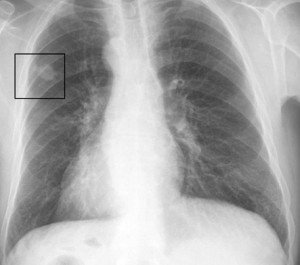

Diaqnostikası

Rentgen, KT, MRT, biopsiya diaqnostikada faydalıdır.

Şəkil

Müalicəsi

Əsas müalicəsi radikal rezeksiyadır. Bəd xassəli plevral eksudatın olması radikal müalicəyə əks göstərişdir. Sarkomaların radikal müalicəsindən sonra 5 illik yaşama 16,8% təşkil edir. Cərrahi müalicə, şüa və kimya terapiya törəmənin histoloji quruluşundan asılı olaraq tətbiq olunur. Yaranmış defektlər dəri-əzələ loskutu və ya sintetik materialla bərpa edilir.